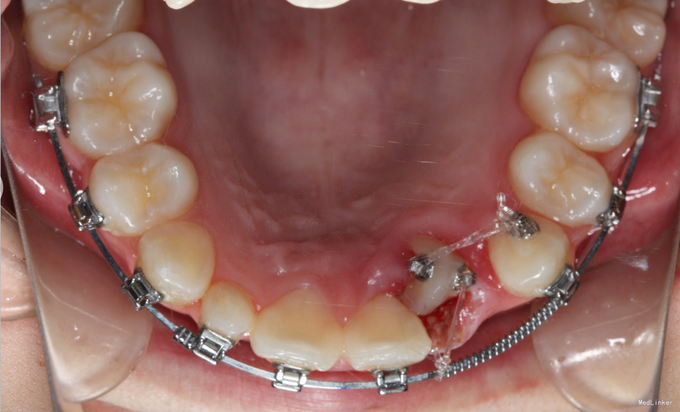

直面型,左上乳2仍存,口内未见恒2,下前牙口内只有3颗。上下牙齿轻度拥挤不齐。全景示下前牙先天缺失一颗,左上恒2垂直埋伏阻生。

诊断:先天缺牙;22牙埋伏阻生 治疗:排齐整平后,拔除乳侧切牙(先保留乳牙不拔的目的是为了保持骨量)然后开窗牵引恒2,先用弹力线逐渐加力,牙齿快移入牙弓的时候粘接拖槽,用12niti的辅弓辅助22牙排齐,同时主弓丝仍为1825ss维持弓形不变。